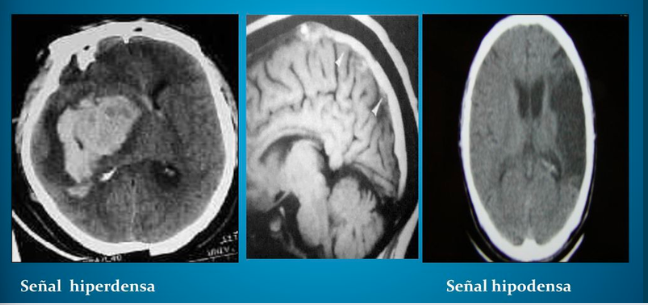

TC

Estudio para identificar rápidamente el sangrado intracraneal e isquemia cerebral aguda.

TC (tomografía computarizada)